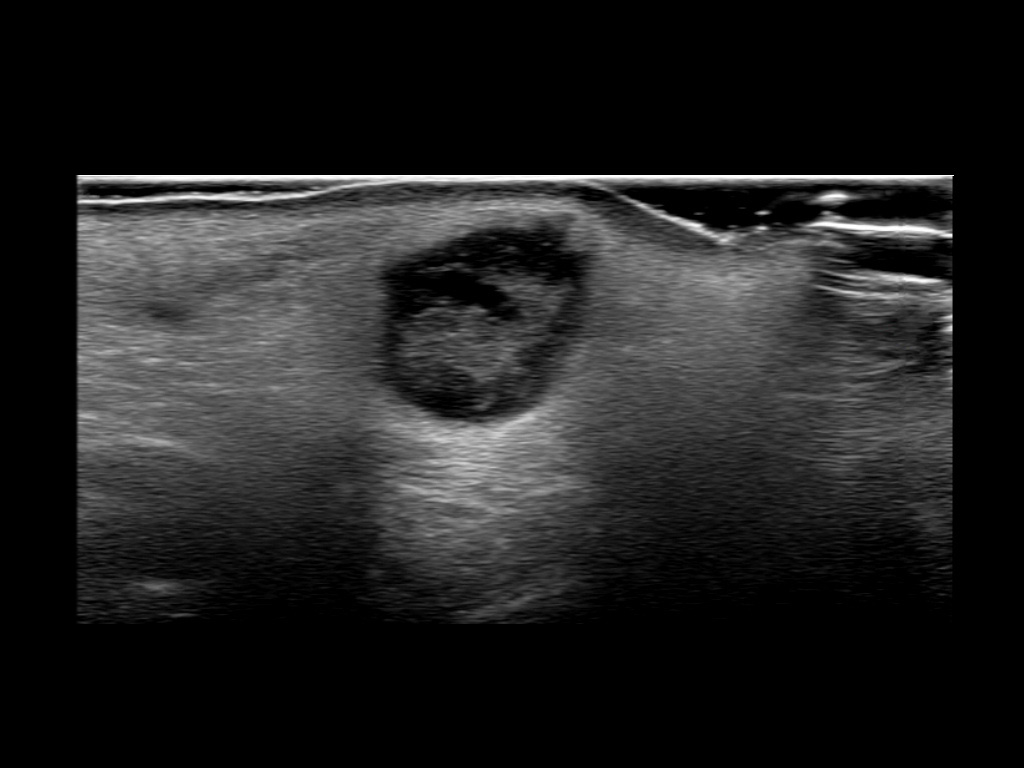

With ultrasound signs of inflammation can be visualized. Edema can be seen as a hyperechoic appearance of the subcutaneous fat, sometimes separated by hypoechoic fluid filled area’s, known as cobblestone appearance. Increased vascularization (hypervascularity) can be seen on colour Doppler. An abscess will appear as a fluid collection appearing as an irregular hypoechoic area with heterogeneous internal echoes and a thickened wall. Posterior acoustic enhancement can be present, and there is vascularity around but not within the mass. Under ultrasound guidance, abscesses can be managed by needle aspirations (18G) under antibiotic cover.

Study the first image to recognize the different layers. If you are sure about the layers, swipe to the second image to view the answer (if applicable).